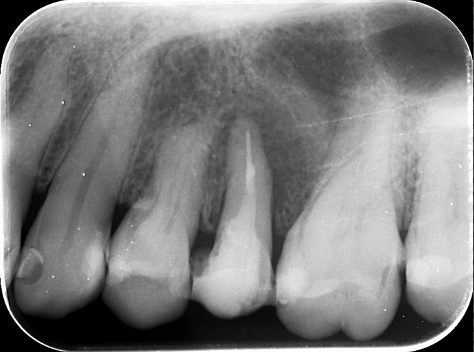

デンタルレントゲン

歯根を取り囲むような黒い影があり、歯根破折を強く疑います。